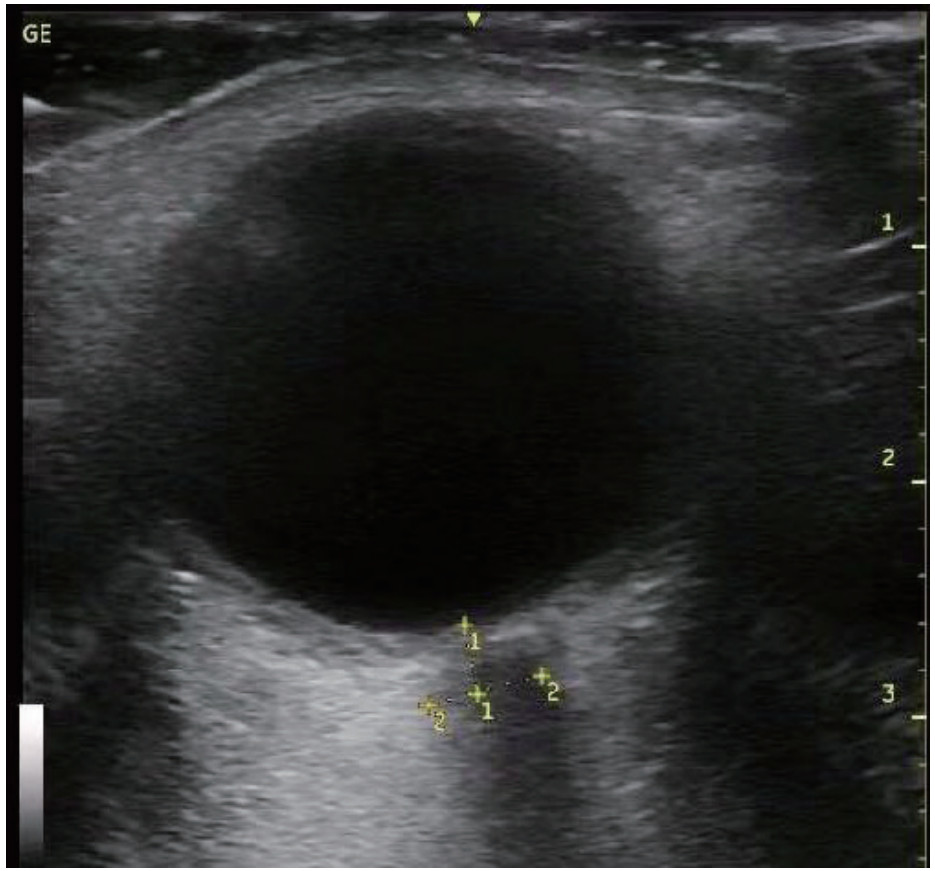

通过查阅电子病历收集CCS患者年龄、性别、是否合并高血压和(或)糖尿病等基础病、急诊入院时头颅CT影像学表现、GCS评分、急性生理学与慢性健康状况评分Ⅱ(APACHE Ⅱ)等基本资料,以及急诊入院后电解质(钾、钠),血液检查指标C反应蛋白(CRP)、葡萄糖(GLU)、肌酸激酶(CK)、肌酸磷酸激酶同工酶(CKMB)、乳酸脱氢酶(LDH)、神经元特异度烯醇化酶(NSE),手术后转入ICU监测床边心脏彩超指标:速度时间积分(VTI)(见图 1)、射血分数(EF),右心Tei指数,术后颅内压(ICP)及相应时间的视神经鞘直径(ONSD),记录术后第3天ICP,并计算ICP变化率=(术后ICP-术后第3天ICP)/术后ICP等临床资料,记录两组患者转入ICU是否使用血管活性药物及用量(重酒石酸去甲肾上腺素注射液生产厂家:远大医药(中国)有限公司,批准文号:国药准字H42021301,规格:2 mg/支),镇静镇痛等治疗用量及平均每日液体平衡量等指标,其中镇痛药物使用注射用盐酸瑞芬太尼(生产厂家:宜昌人福药业有限责任,批准文号:国药准字H20030197,规格:1 mg/瓶),镇静药物为丙泊酚注射液(生产厂家:西安力邦制药有限公司,批准文号:国药准字H19990282,规格0.2 g/支)。心脏彩超及ONSD测量均为本院通过重症超声规范化培训并取得合格证书者完成,心脏彩超测量采用EDGE型彩色多普勒超声仪(美国索诺声公司)检测,其中Tei指数是由多普勒超声衍生而出的时间间期指数,定义为等容收缩时间(ICT)与等容舒张时间(IRT)之和除以射血时间(ET)。Tei指数的计算公式:Tei指数=(ICT+IRT)/ET。连续测量3次取平均数。ONSD采用EDGE型彩色多普勒超声仪(美国索诺声公司)高频(5.0~10.5 MHz)线阵超声探头测量眼球后3 mm位置视神经鞘的宽度,并反复测量3次取平均值(见图 2)。

图 2 超声下视神经鞘直径测量(ONSD) Fig 2 Measurement of optic nerve sheath diameter under ultrasound (ONSD)